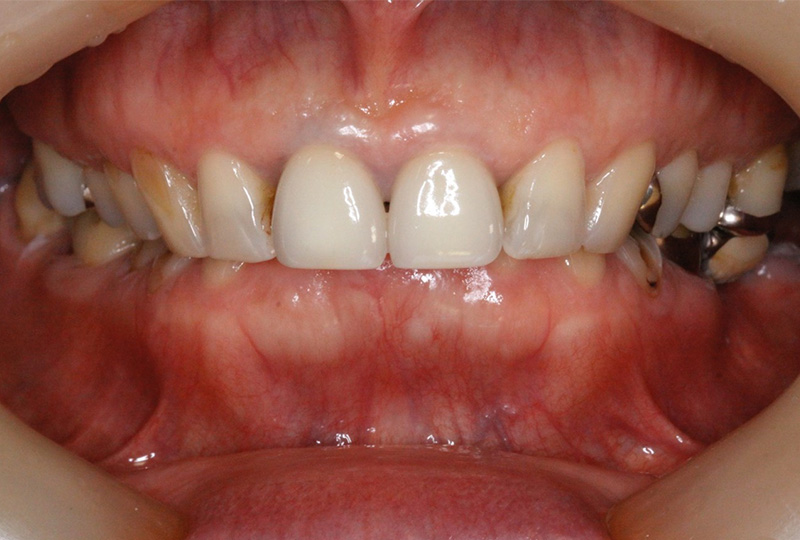

審美性にこだわった治療から保存が難しいと言われた歯の保存やお口全体をより良い状態にする一歩進んだ専門的な治療を行います。